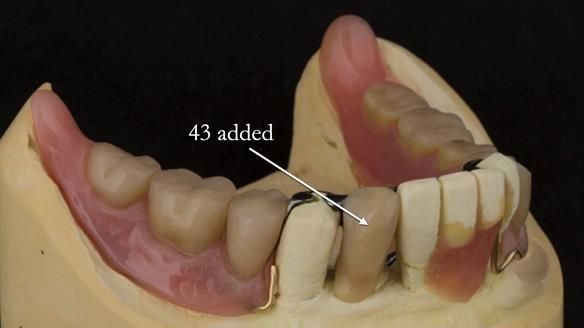

In 2022, tooth 43 fractured.

An artificial tooth was added to the RPD

by welding a cobalt–chrome tag to the bar

and adding the tooth.

The denture continued to function extremely well.